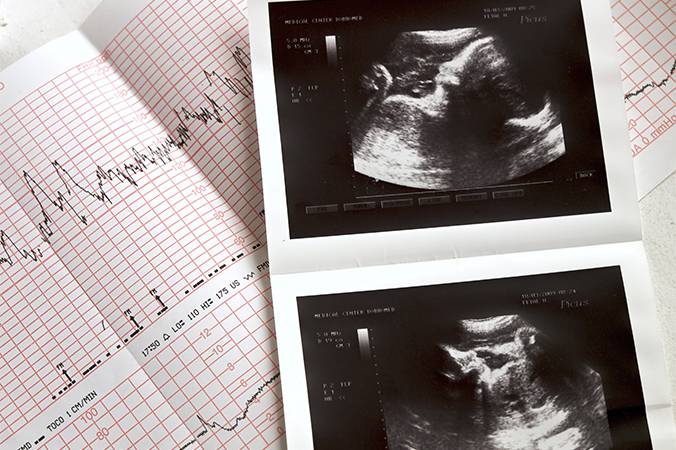

O ecocardiograma fetal é um exame essencial para a avaliação da saúde do coração do bebê ainda no útero. Rápido, indolor e seguro para a mãe e o feto, o procedimento fornece imagens detalhadas do órgão em formação, permitindo ao profissional identificar possíveis alterações nas válvulas cardíacas, músculos e fluxo sanguíneo.

A detecção precoce de malformações cardíacas possibilita o planejamento adequado do parto, o acompanhamento especializado durante a gestação e, em muitos casos, intervenções que aumentam significativamente as chances de sobrevida e qualidade de vida do bebê.